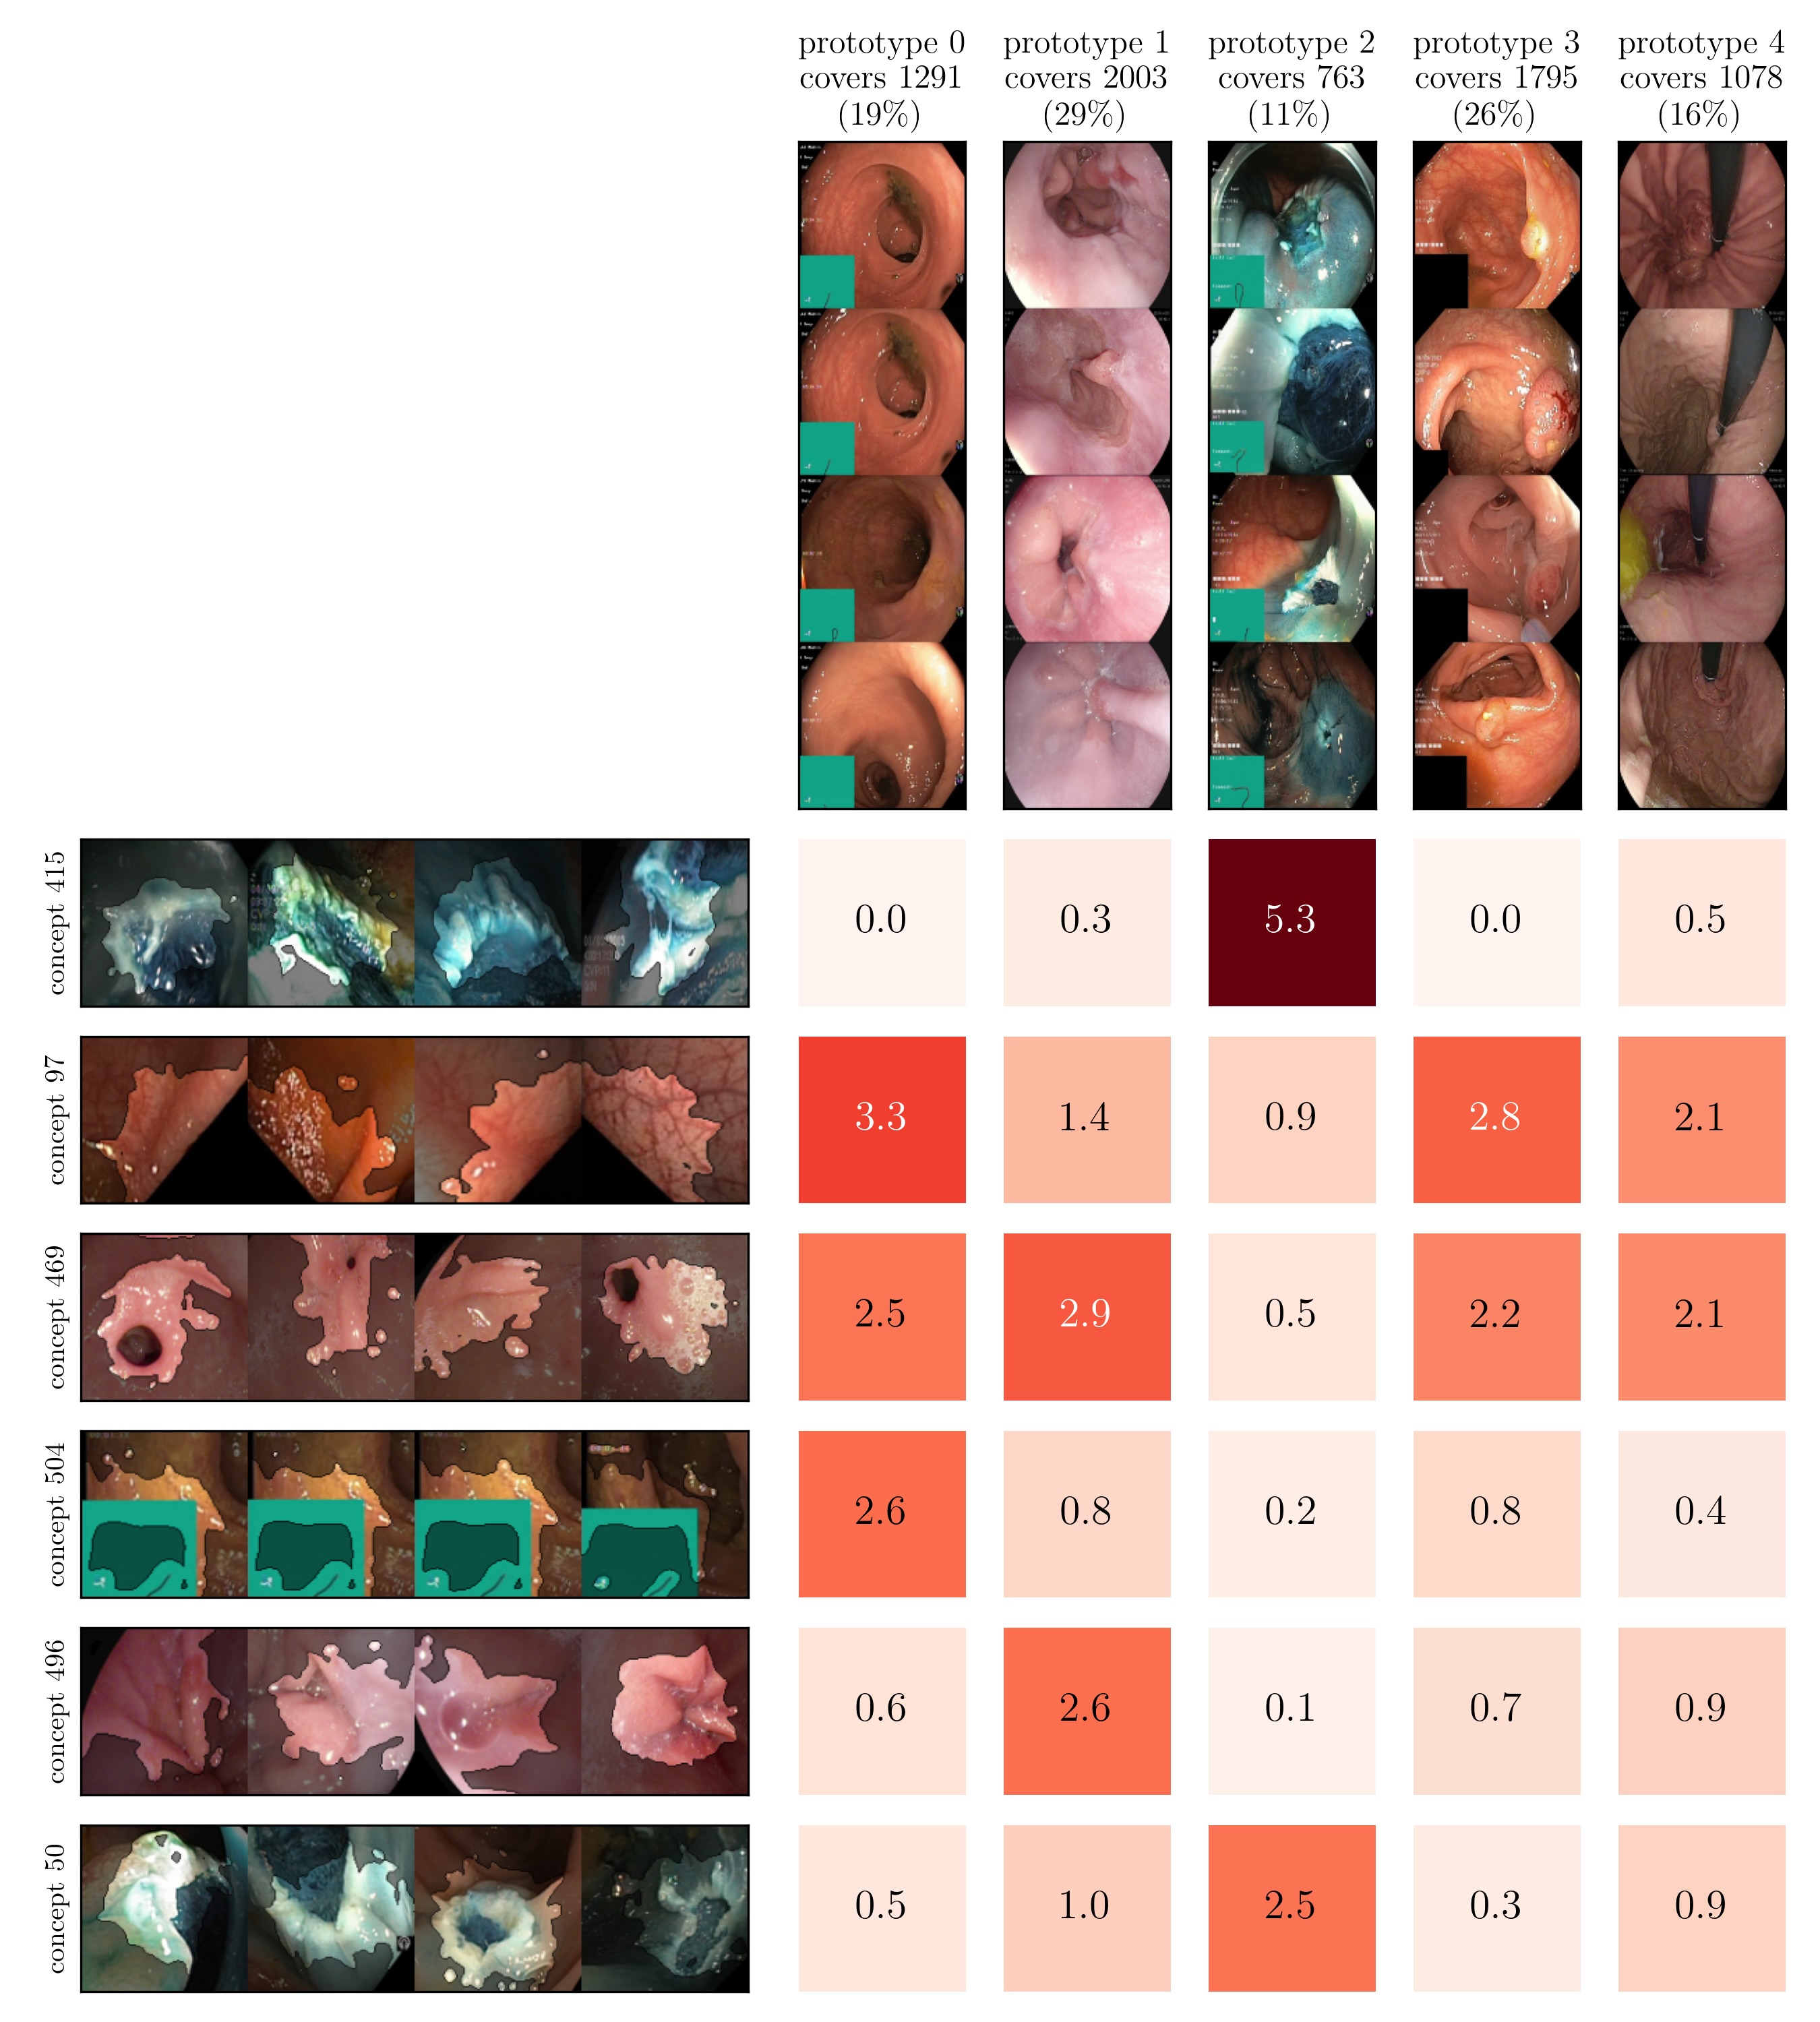

For example, Prototypical Concept-based eXplanations (PCX) [27] train Gaussian Mixture Models on max-pooled latent relevance scores and consider cluster means as stereotypical explanation, encoded as distribution over concepts (i.e., neurons).

Both input and latent relevance clustering require subsequent human supervision to determine whether outlier clusters represent valid or spurious behavior. To semi-automate this process, Anders et al. [3] propose using Fisher Discriminant Analysis [37] to rank class-wise clusterings by linear separability, while Dreyer et al. [27] computes similarities between prototypes. The results of clustering approaches can serve as an initial set for bias modeling methods outlined in Sec. 3.2, which can be refined iteratively. An example outlier cluster of latent relevances is shown in Fig. 4 (top), with all samples containing the spurious band-aid concept.

6.2 Concept Validation: Identification of Spurious Behavior

Given the fitted models, we apply bias identification methods introduced in Sec. 4 to detect the expected spurious model behavior. Throughout this section, we focus on the ResNet50 model trained on ISIC2019 with various confounders. We further limit our analyses to samples from the melanoma class to prevent that clustering model behavior results in clusters representing different classes, and instead allowing us to identify spurious sub-strategies for predicting the considered class.

Data Perspective

We first apply SpRAy in input and latent space, computing input feature importance scores using LRP summed over color channels. To obtain latent relevances, we use intermediate relevance scores in the LRP computation process after the (out of four) residual block, max-pooling over spatial dimensions to yield relevance scores for layer with channels. The clustering of pairwise cosine distances between heatmaps is shown in Fig. 6 (top left). Detected outlier clusters contain samples with spatially coherent biases, e.g., the black circle around the lesions originating from microscopes (). In contrast, clustering latent relevance scores reveals more complex, less spatially dependent clusters, as shown in Fig. 6 (top right), including the ruler artifact () and the microscope (). Compared to those in input space, the cluster for the microscope in latent space represents a more diverse high-level concept. In the input space visualization, we further highlight samples from the ruler cluster detected in latent space. Instead of forming a cluster, they spread across the entire embedding space, indicating that the bias is too complex to be detected in input space.

Model Perspective

Next, we apply bias identification approaches from the model perspective by identifying outlier neurons based on activation pattern via DORA and relevance pattern by clustering pair-wise cosine distances between concept relevance scores. We focus on latent activations and relevances after the third residual block. DORA uses a distance function based on how neurons activate upon each others n-AMS, achieving high similarity when neurons activate upon similar input signal. A 2D visualization of the resulting distance matrix is shown in Fig. 6 (bottom left). Identified outlier concepts include ruler () and (white) hair (). We further compute pairwise cosine distances between latent relevance scores , aggregated over spatial dimensions, and apply UMAP to embed the resulting distance matrix in . This results in high similarity between neurons (concepts) that the model uses similarly for predictions. The concept clustering is visualized in Fig. 6 (bottom right), highlighting two outlier clusters focused on rulers () and blueish tint ().

Results for other classes, model architectures, and datasets are presented in Appendix A.6.1. This includes experiments with ECG data in Fig. 10, revealing the artificially inserted static noise in the attacked lead from both data and model perspectives. Notably, dominant spurious concepts, such as the artificial timestamp in HyperKvasir or the static noise in PTB-XL, may not be detected as outlier concepts. In such cases, analyzing prediction sub-strategies via PCX may provide additional insights on spurious inlier behavior. Hard-to-interpret concept representations pose another challenge for the model perspective. For example, the brightness artifact in CheXpert is not clearly visible in the concept UMAP (see. Fig. 15, right), but can easily be detected using SpRAy (Fig. 15, left) or PCX (Fig. 22). In summary, while all considered spurious features are detected, the choice of bias identification approach is crucial, as some shortcuts are easier to detect as outlier concept (e.g., ruler) and others via PCX (e.g., brightness, static noise in ECG).